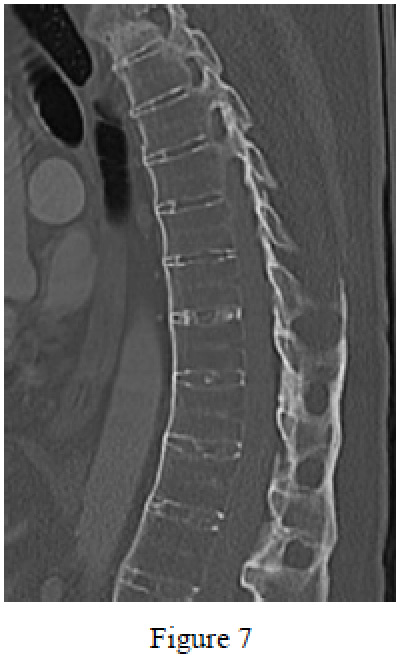

Question 7

Figure 7 is a sagittal CT scan of a 28-year-old man who is being evaluated for spinal and peripheral joint issues. Which medication is most appropriate to initiate at this time?